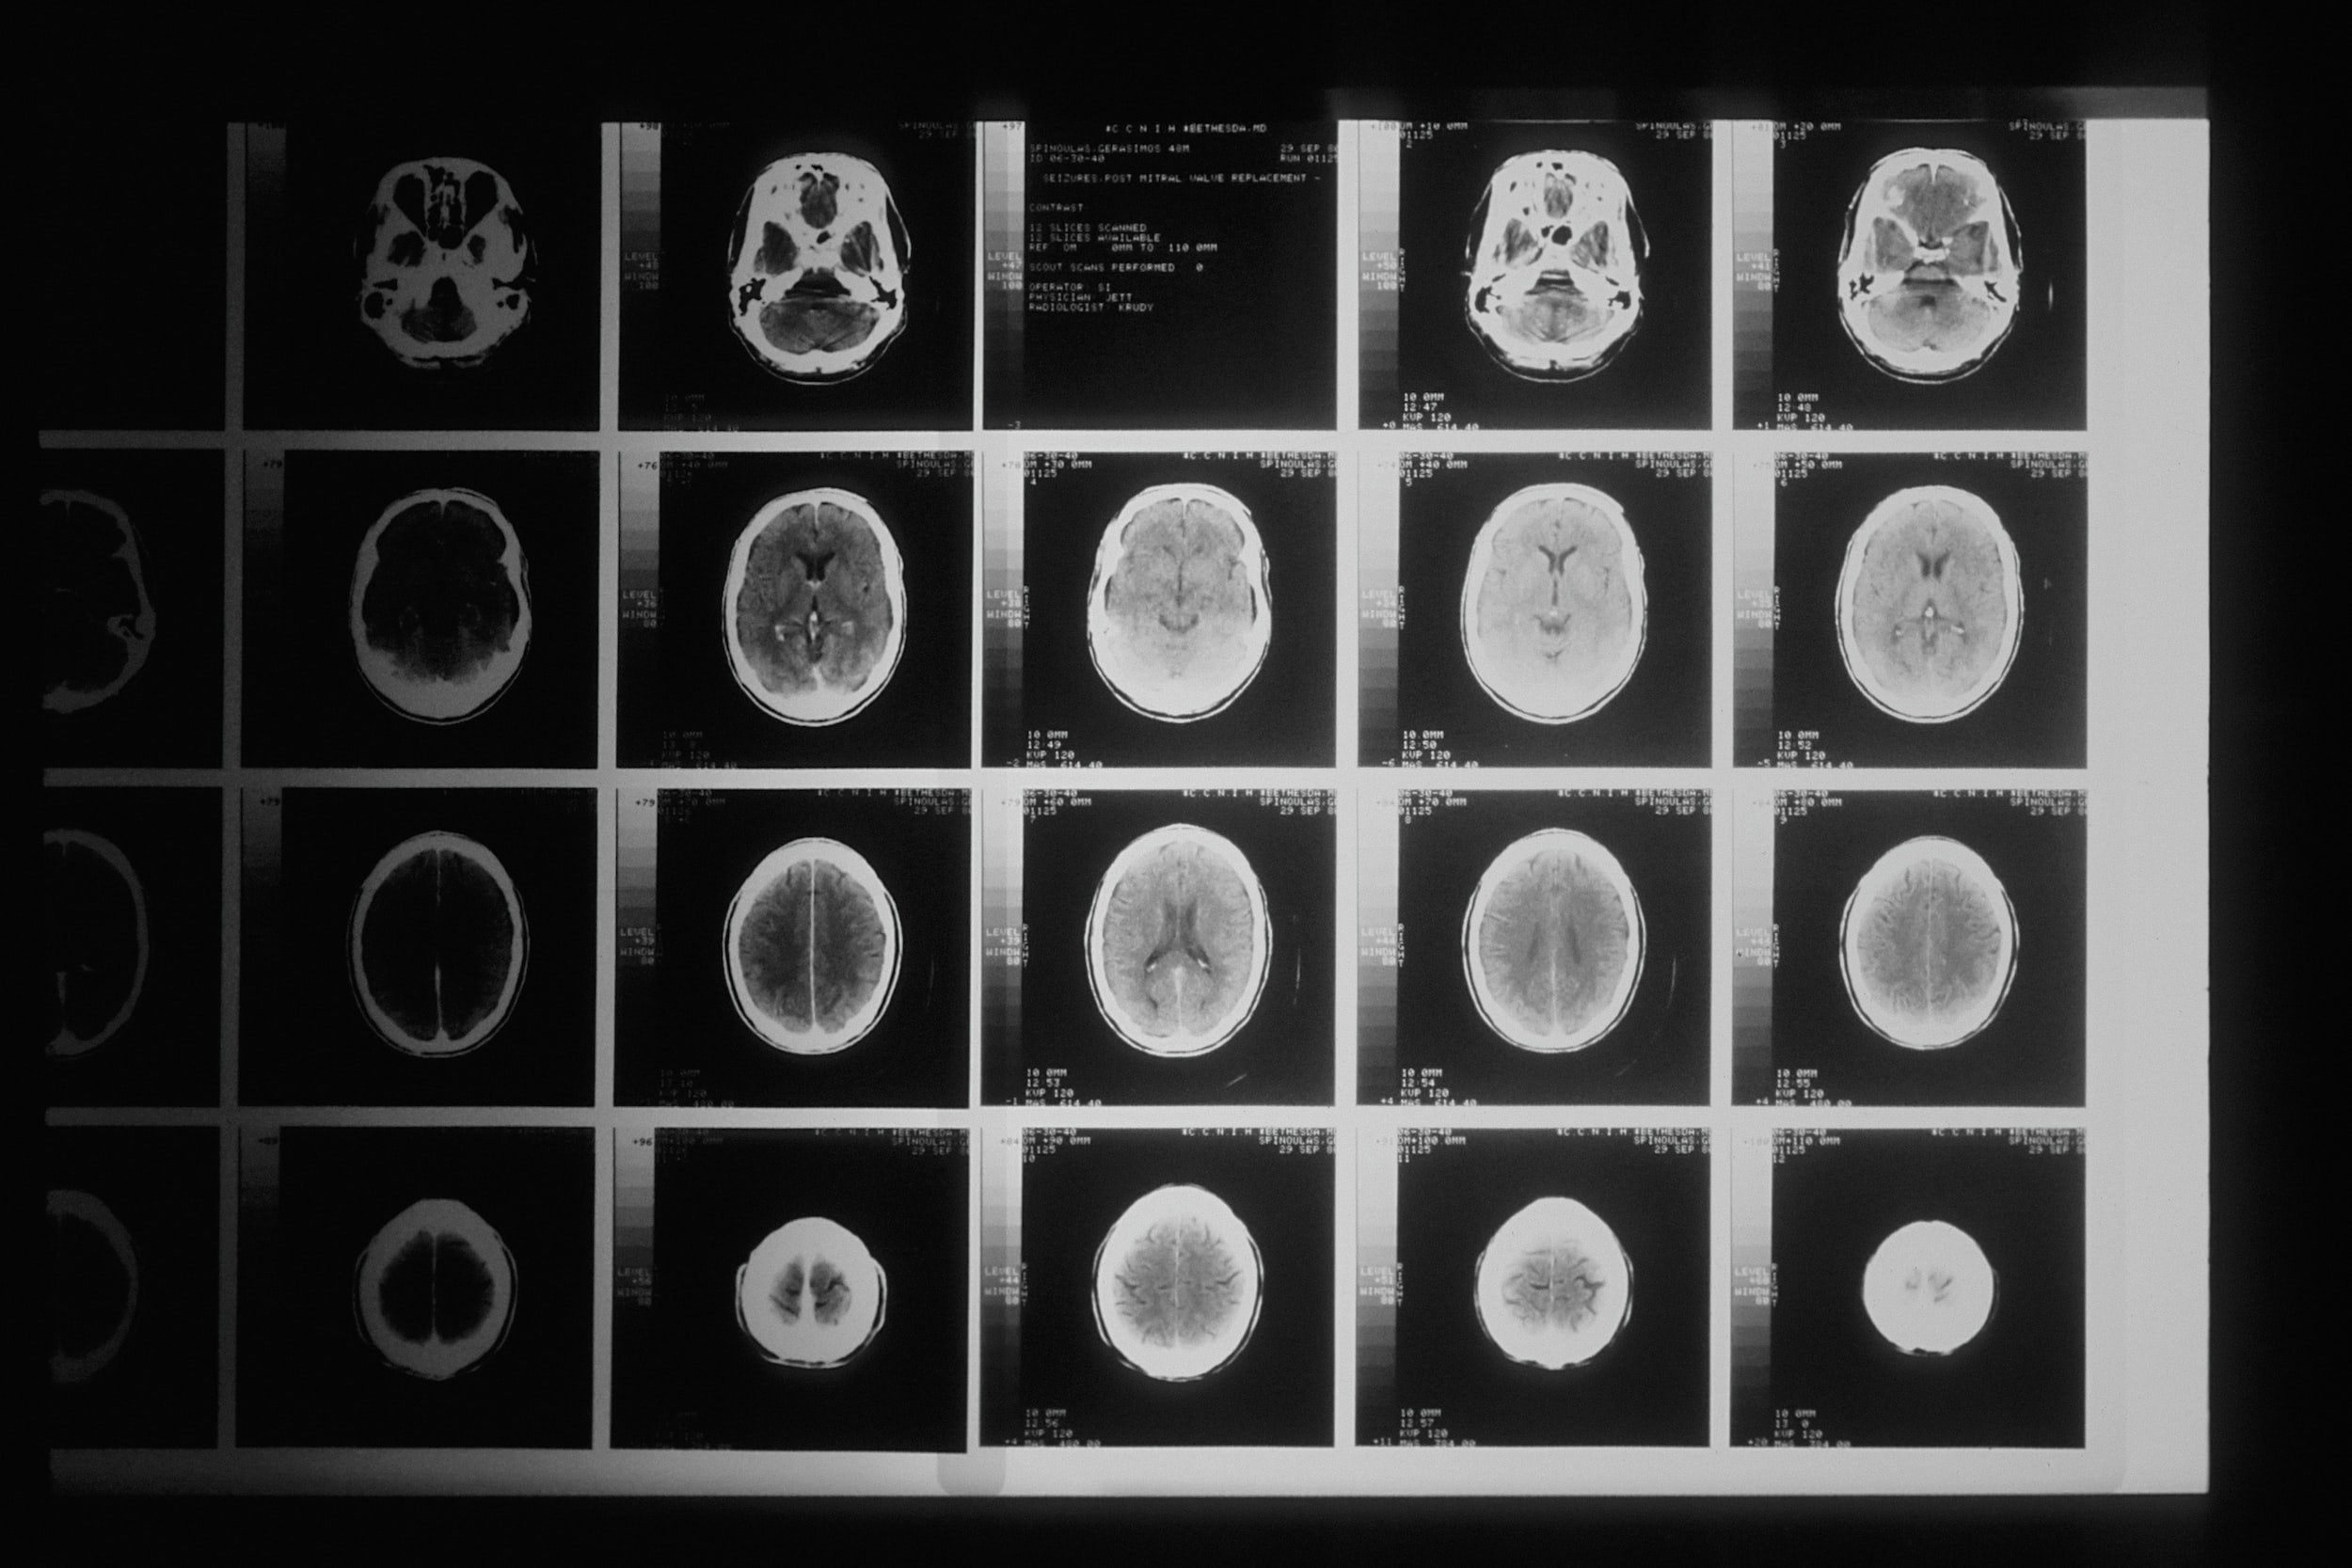

The neurologist called me into his office after 90 minutes and he had completed the review of the MRI scans and he showed me the various images of my brain (Image below is an example of an MRI head scan). My wife did comment that it was a great achievement to find the brain, but the good news was the scan was normal and no damage or abnormality to the brain.  “However, can I ask what you have done to your nose?” asked the consultant ….” My nose?”. He then showed me a vertical scan of my head and you could see a few cracks in my nose and a small piece of flapping bone. I explained that I broke my nose a few times playing rugby in the past, but it could also explain why my wife complains of a clicking noise when I sleep on my right-hand side. The neurologist smiled and guessed that the air in my nostril was probably causing the flapping bone to make that clicking noise. This is still on my to do list to try and resolve and as the neurologist explained it is more cosmetic than critical, but it could be a lot cheaper than a divorce!

Example of a brain scan

Example of an brain scan from the MRI scanner

Update: The National health service in the UK is under immense pressure due to the pandemic and funding and resourcing for mental health and wellbeing has reduced at a time when mental health issues have increased. The pandemic has impacted everyone in the world, and everyone has been impacted by worry, stress and anxiety and from comments on my social media people are really struggling to get help.  I am not an expert but for me personally I knew that my mind was under pressure from work and losing my dad and I was confident that with the correct support I would improve but I also know that every individual situation is different. Just looking at my brain scan in various angles really illustrated to me how complex and amazing the brain and mind is and how powerful and instrumental it is for our health and wellbeing.